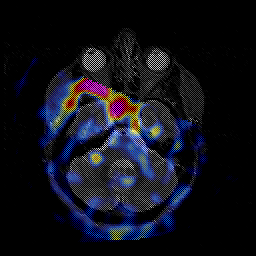

Glioblastoma multiforme overlay -- Slice #16

[Home][Help][Clinical][Tour 1][Tour 2][Tour 3] Slice 16